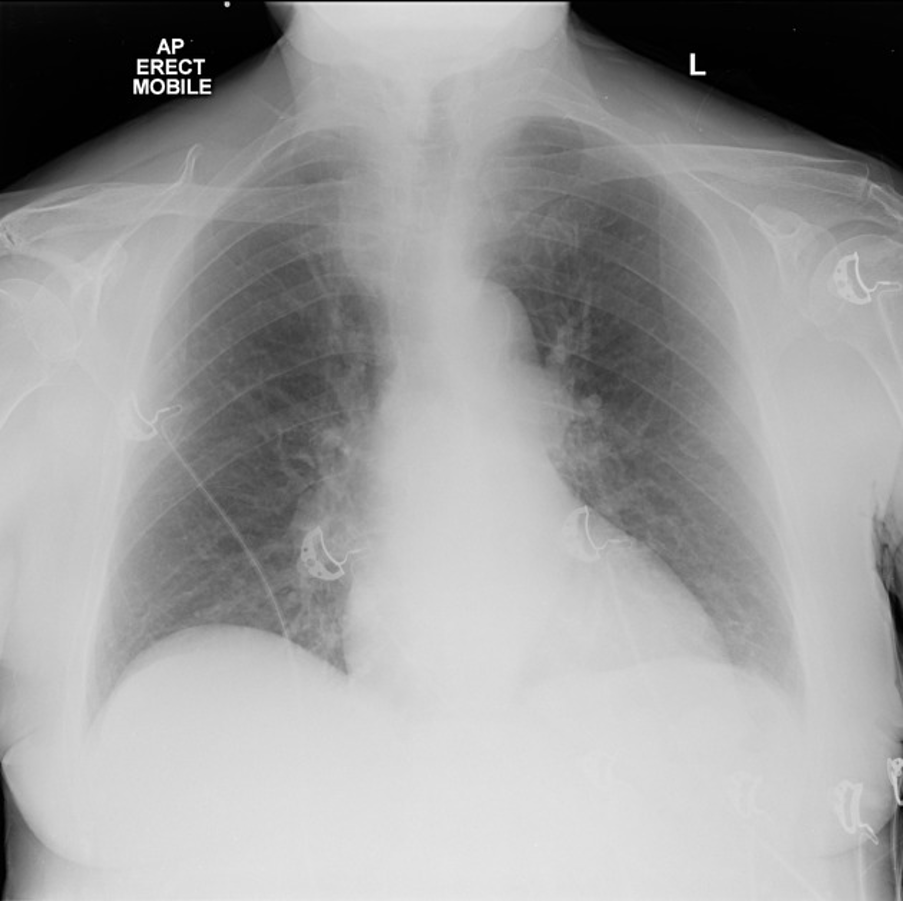

- CXR to rule out other causes if diagnostic uncertainty e.g. infection, pneumothorax

Case courtesy of Craig Hacking, Radiopaedia.org, rID: 41942

No evidence of focal consolidation or pneumothorax, chest clear. Normal CXR.